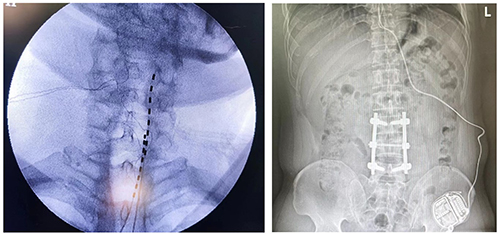

小谢收治住院后完善相关检查,诊断为“神经病理性疼痛:幻肢痛”。因小谢及家属对疼痛的治疗和缓解有着十分强烈的渴求。科主任黄东及副主任胡蓉立刻组织科室医护人员联合讨论患者病情。经过全面的评估,制定了给患者置入永久性脊髓刺激器的方案。患者首先于8月8日行一期临时电极置入,测试有效。于8月17日完成二期永久刺激器的置入。

图为置入电极和永久刺激器的X线片

术后接近一个月,小谢的疼痛缓解达到百分之八十以上,再也没有出现反复发作导致汗如雨下、痛不欲生的感觉了。 “感谢你们疼痛科,为我祛病除痛。”小谢的脸上也出现了久违的笑容。